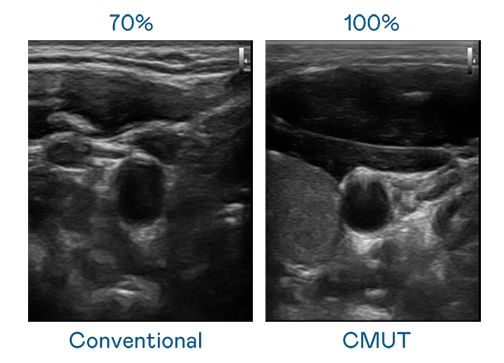

CMUT 技術是一種用電容式微機電元件來產生超音波訊號的技術。與傳統 PZT 壓電式技術相比,CMUT 頻寬增加 30%,更寬頻的超音波訊號讓影像解析度大幅提升,是實現高影像品質醫療超音波掃描、促進精準醫療發展的關鍵技術。

超音波影像的解析度高低,首先取決於探頭能發出的訊號頻寬。J9九游 CMUT 可提供高清晰的超音波訊號,提供高頻寬、高靈敏度、影像紋理細節更高的超音波影像,協助醫護人員縮短影像判讀時間及利用精準的醫療影像進行診斷。